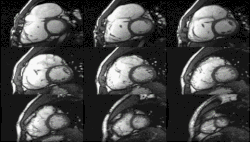

Enlarged right ventricle with poor function in a patient with repaired tetralogy of Fallot by CMR